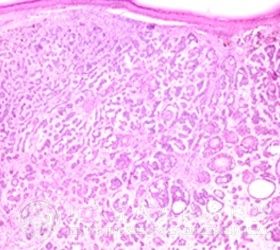

专家服务:外阴基底*癌多发生于大小阴唇、阴蒂,前庭部位比较少见,较少情况下也可发生于会阴。其症状主要有以下几个方面:

2、外阴基底*癌常表现为小的病灶,早期一般呈灰色,几乎有些半透明,位于变薄的上皮下,小结节直径常常小于2厘米。本病常有3种基本类型,即结节溃疡型、扁平型、息肉型。

外阴基底*癌的诊断可根据临床表现,一般比较容易诊断,但也需作病理组织学检查方可确诊。北京京城皮肤医院提醒大家,外阴基底*癌病程缓慢,容易复发,要引起大家的重视。